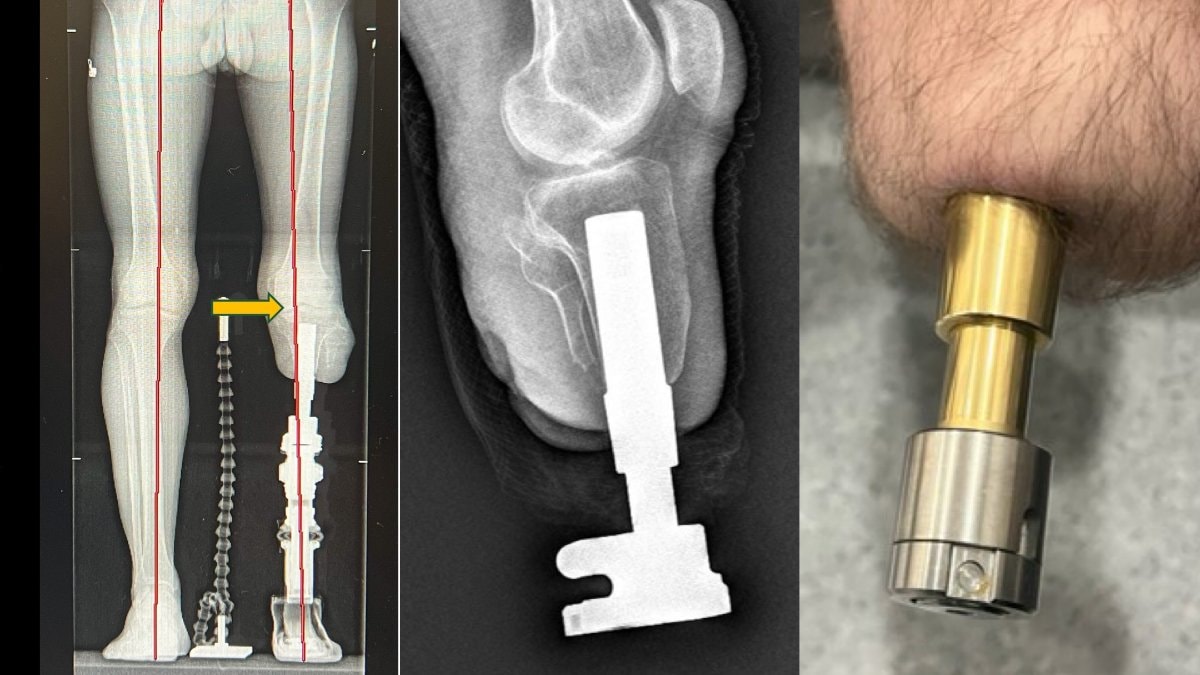

Kemiğe yerleştirilen implantlarla daha doğal ve konforlu bir yürüyüş sunan bu yöntem Türkiye’de de uygulanıyor.

Bu yöntemde, kemiğe yerleştirilen implant sayesinde yük doğrudan kemiğe aktarıldığından, çok daha doğal ve konforlu bir yürüyüş mümkün oluyor.

Osseointegrasyon protezlerinin yapıldığı uzuvlar hakkında da bilgi veren Prof. Dr. Kara, yöntemin uyluk, kaval kemiği, dizüstü ve dizaltı gibi bölgelerin yanı sıra üst kol amputasyonlarında da başarıyla uygulandığını aktardı.

Kullanım süresi hakkında da bilgi veren Prof. Dr. Kara, “Bu protezlerde yalnızca dış parçalar zamanla değiştiriliyor. Suya dayanıklı modeller sayesinde hastalar denize bile girebiliyor. Günlük hayatlarına yakın bir yaşama dönüş mümkün oluyor” dedi.